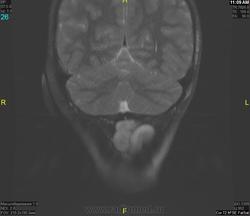

Уважаемые коллеги! Прошу консультативной помощи. Про пациента известно: девочка (7 лет), в анамнезе 2,5 года назад травма головы. Не диагностировалась. Периодически жалобы на болезненность при пальпации затылочной области(((((

Напоминает сосудистую структуру.Может, какая-нибудь лимфангиома?Видела на передней поверхности шеи, на задней - нет.

как будто связь с ликвором имеется.  Дополнил бы венографией, и FatSat"ом ну и контрастом, конечно.

Сегодня в ходе разговора с мамой девочки, выяснилось, что и у мамы есть подобное "образование". С ее слов, несколько лет назад ей делали пункцию для исключения онкологии. Результат пункции: содержится нервная ткань и лимфоциты ( опять же никаких документов я не видела). То есть можно говорить о наследственном характере.

Нейрофиброма вполне может быть. Плексиформная. Проверить на нейрофиброматоз. Я видел такой же структуры и локализации. Пятен на коже нет? Вообще на теле? И нет ли чего похожего в позадиглоточном пространстве?

есть похожее образование в позадиглоточном пространстве)

многоузловое образование  исходящее из задней части предпозвоночного пространства с переходом на подкожную жировую клетчатку головы!шваннома ,нейрофиброма и их злокачественные аналоги